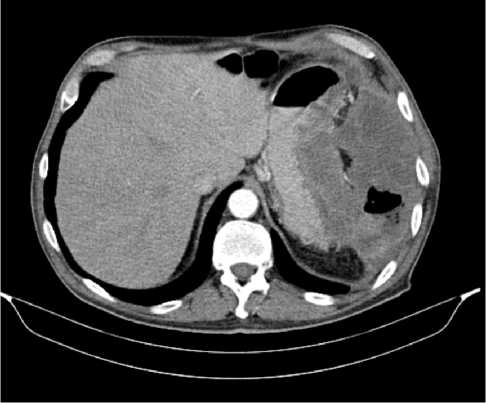

Выполнена компьютерная томография (КТ) органов грудной клетки, брюшной полости в июле 2019 г. Инфильтративных изменений в легких не обнаружено. Выявлено новообразование антрального отдела, малой кривизны и передней стенки желудка, распространяющееся на заднюю стенку, преимущественно на препилорический отдел. Имелись признаки локального перехода образования на большой сальник, гепатодуоденальную связку с периваскулярным ростом и признаками лимфоваскулярной инвазии. Многочисленные забрюшинные ЛУ сливались между собой в конгломераты размерами до 40 × 29 мм с частичным вовлечением почечных артерий. Также билобарно обнаружены немногочисленные очаговые образования в печени до 10 мм. Высказано подозрение на перитонеальный канцероматоз (рис. 3).

Рис. 3. Результаты компьютерной томографии органов брюшной полости у пациента 80 лет с диагнозом метастатический рак желудка с признаками микросателлитной нестабильности (июль 2019 г., до лечения)

Fig. 3. Results of a CT scan of the abdomen in an 80-year-old patient with metastatic MSI-H gastric cancer (July 2019, before treatment)

В результате обследования был установлен диагноз рака антрального отдела желудка (c)T4аN3вM1. По решению онкологического консилиума, учитывающего молекулярно-генетический профиль опухоли, а также возраст пациента, выраженность сопутствующей патологии (в анамнезе острое нарушение мозгового кровообращения (ОНМК), острый инфаркт миокарда (ОИМ), фибрилляция предсердий (ФП), постоянная форма), ограничивающей проведение ПХТ, была начата ИТ 1 линии пембролизумабом. С сентября 2019 г. по декабрь 2021 г. проведено 29 циклов ИТ 1 линии по схеме пембролизумаб в монорежиме с максимальным эффектом частичный регресс (рис. 4). Осложнений лечения не зарегистрировано.